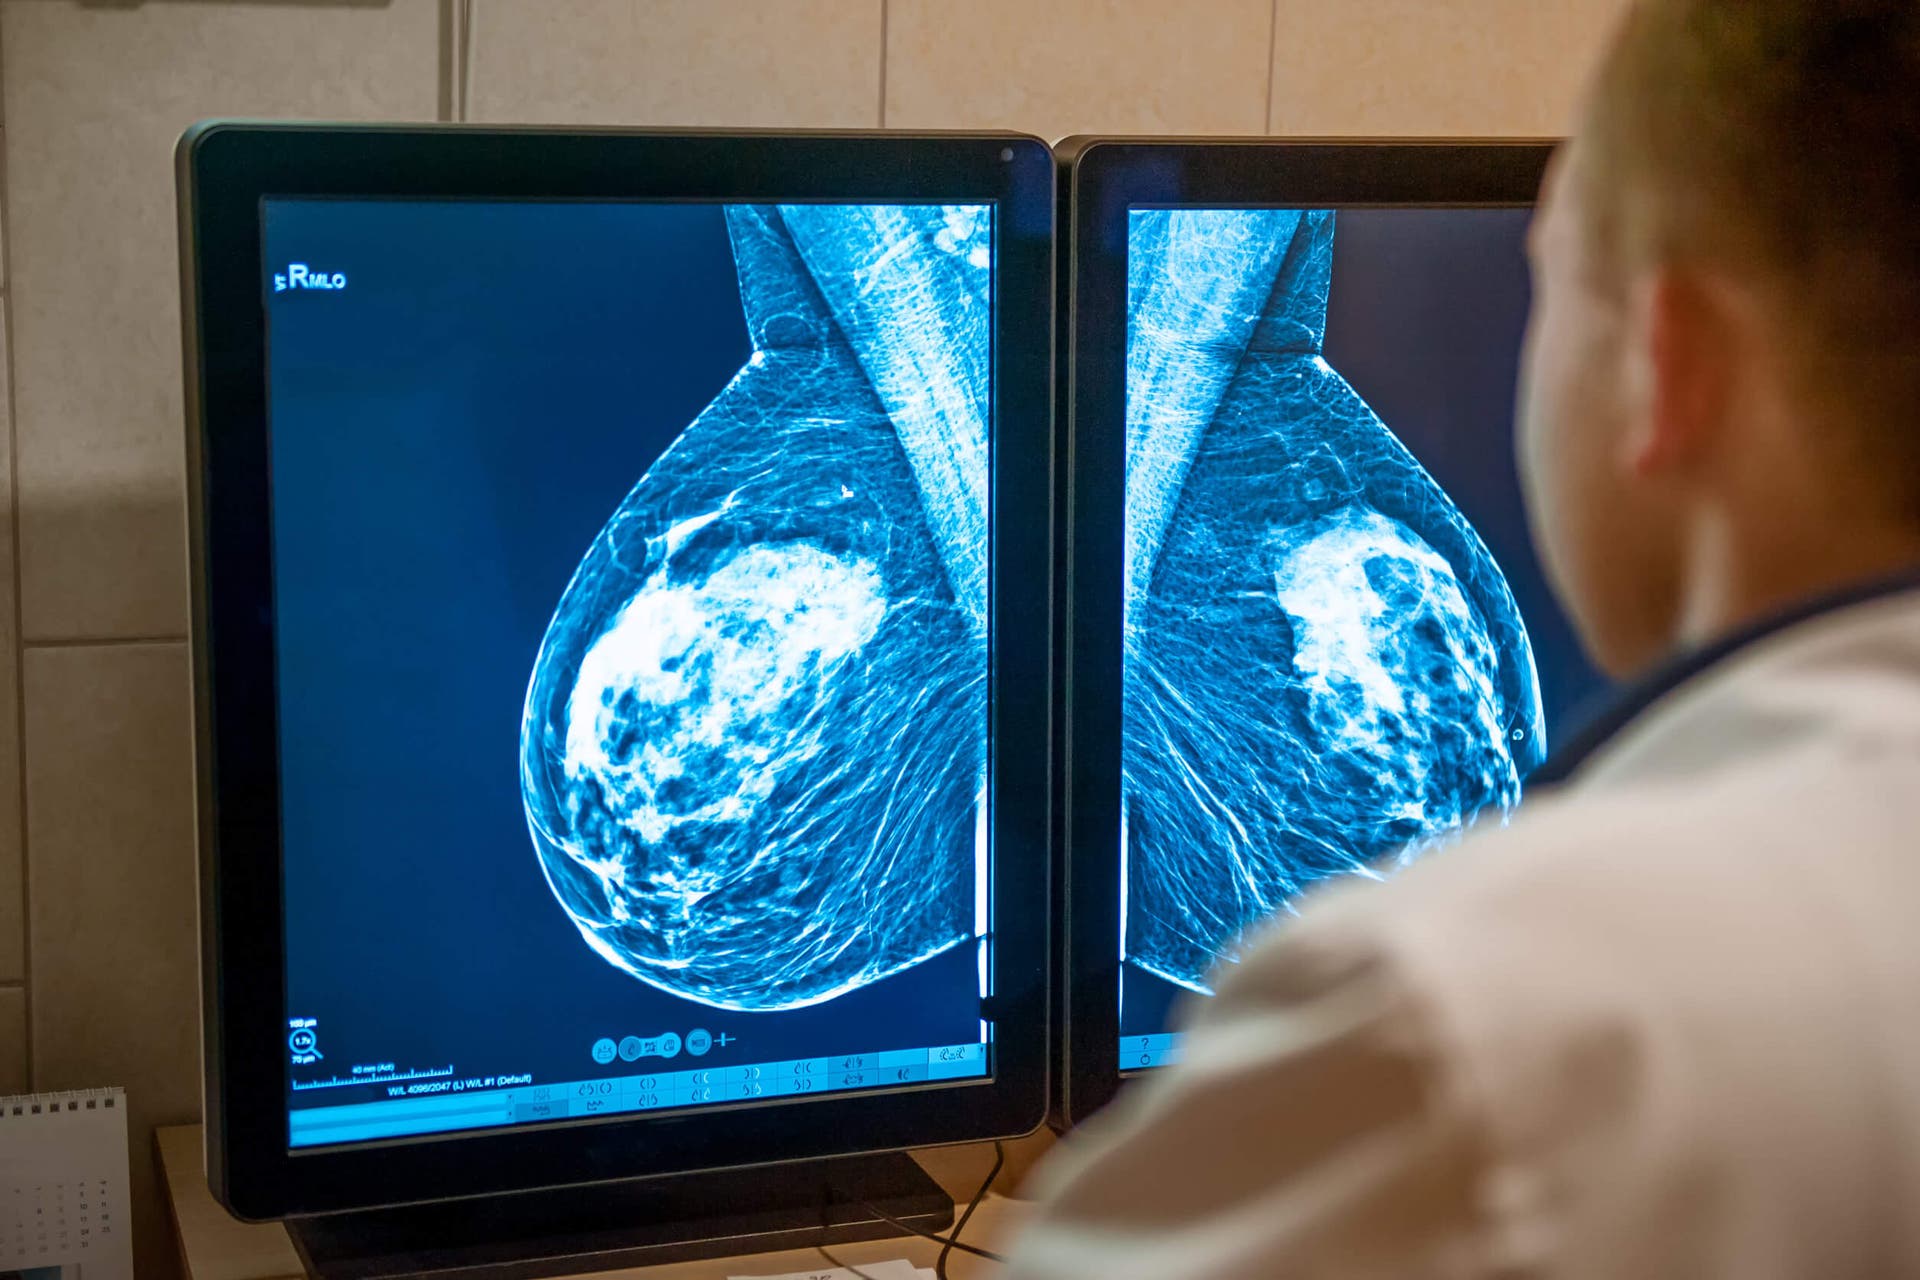

En principio, realizarían una mamografía, pero ameritó complementar con una ecografía. El informe del ultrasonido refirió imágenes preocupantes, derivando de esta manera en una triple biopsia urgente. Todo ocurrió en el mismo día: 8 de marzo, fecha en que las pruebas confirmaron a la organizadora profesional que tenía cáncer.

La mamografía, la ecografía y la resonancia magnética son enumeradas por la Revista Médica Sinergia como otros métodos para un dictamen médico con relación al cáncer.

En contextos con recursos suficientes, la Organización Panamericana de la Salud (OPS) sugiere programar el tamizaje con mamografía cada 2 años. Para entornos cuyos recursos limiten el estudio de imágenes, el examen clínico es una opción. Las edades de inicio en estas consultas varían según los lineamientos sanitarios de cada país.